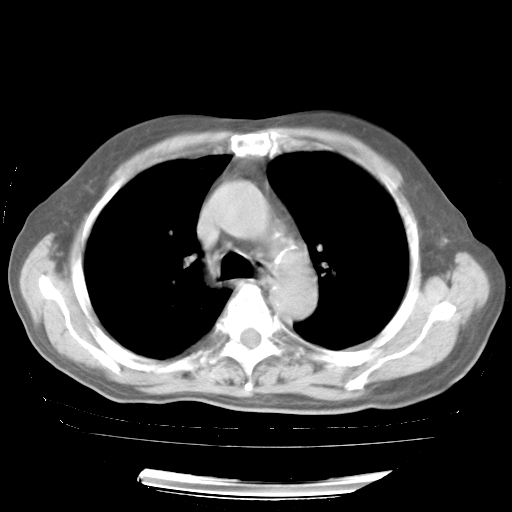

4月28日肺部CT——再次出现类似去年5月9日——磨玻璃样、间有“粟粒样”改变。

4月28日肺部CT